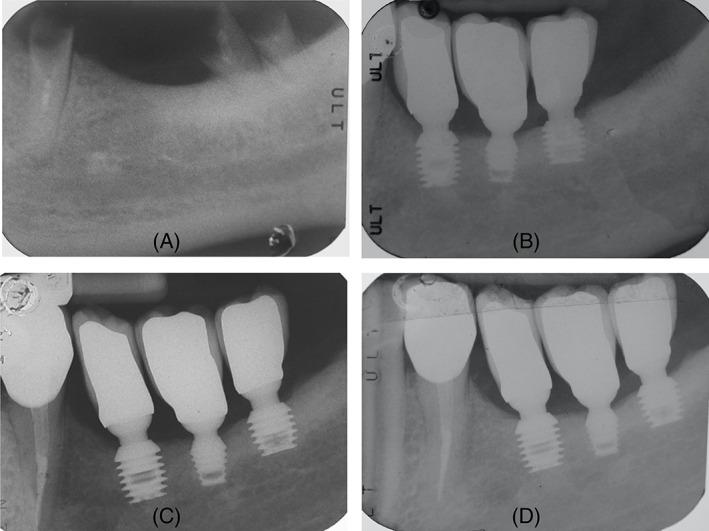

The aim of this retrospective study was to evaluate implant survival, marginal bone loss, and peri-implant complications in 333 locking-taper short and ultra-short implants.

Implants were placed in the maxillary and mandibular posterior regions of 142 patients. Clinical and radiographic examinations were performed at 5-year recall appointments.

All implants placed consisted of 8.0-, 6.0-, and 5.0-mm length, 38.14%, 34.53%, and 27.33%, respectively. Three hundred thirty-two implants (one early failure) were rehabilitated with single crowns in 141 patients. In 45.48% of the implants the crown-to-implant ratio was ≥2, with a mean value of 1.94. Overall implant-based survival after 5 years of follow-up was 96.10%: 96.85%, 95.65%, and 95.60% for 8.0-, 6.0-, and 5.0-mm length implants, respectively (p = 0.82). Overall patient-based survival was 91.55%. Regarding crestal bone level variations, average crestal bone loss and apical shift of the "first bone-to-implant contact point" position were 0.69 and 0.01 mm, respectively. Setting the threshold for excessive bone loss at 1 mm, during the time interval from loading to follow-up, 28 implants experienced loss of supporting bone greater than 1 mm: 19 of them (67.85%) were surgically treated with a codified surgical regenerative protocol. After 60 months, a peri-implantitis prevalence of 5.94% was reported, with an overall implant success of 94.06%: 95.93%, 92.73%, and 93.10% for 8.0-, 6.0-, and 5.0-mm length implants, respectively (p = 0.55).

本回顾性研究旨在评估 333 个锁定锥形短种植体和超短种植体的种植体存活率、边缘骨丧失和种植体周围并发症。

将种植体放置在 142 名患者的上颌和下颌后牙区。在 5 年的随访中进行临床和影像学检查。

所有植入物的长度分别为 8.0mm、6.0mm 和 5.0mm,分别占 38.14%、34.53%和 27.33%。141 名患者的 332 个种植体(1 个早期失败)采用单冠修复。在 45.48%的种植体中,冠-种植体比≥2,平均值为 1.94。5 年随访后,种植体总存活率为 96.10%:8.0mm、6.0mm 和 5.0mm 长度的种植体分别为 96.85%、95.65%和 95.60%(p=0.82)。种植体总存活率为 91.55%。关于牙槽骨水平的变化,平均牙槽骨丧失和“第一个骨-种植体接触点”位置的根尖移位分别为 0.69mm 和 0.01mm。在从加载到随访的时间间隔内,将骨量过度丧失的阈值设定为 1mm,28 个种植体经历了大于 1mm 的支持骨丧失:其中 19 个(67.85%)采用编码的外科再生方案进行了手术治疗。60 个月后,报告了 5.94%的种植体周围炎患病率,总体种植体成功率为 94.06%:8.0mm、6.0mm 和 5.0mm 长度的种植体分别为 95.93%、92.73%和 93.10%(p=0.55)。